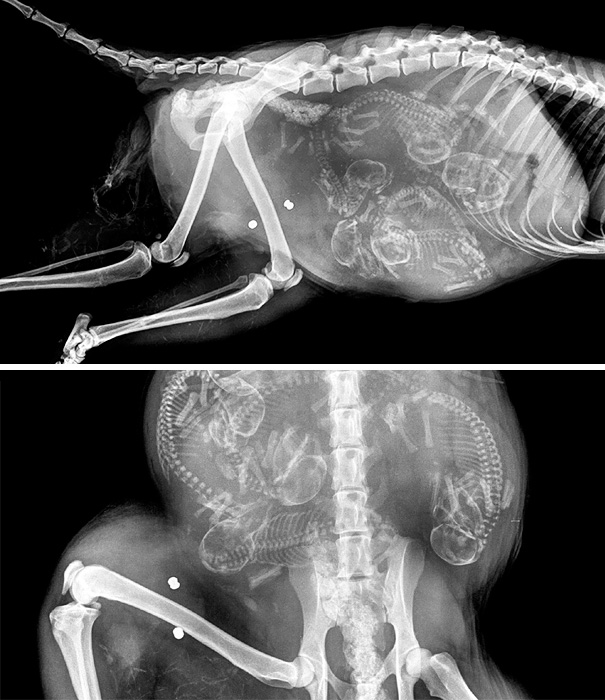

Pregnant Dog X-Ray

These are easier to see then the preg kitten. Looks like a lot of pups in there!

I hope I can't count. There's more puppies then she'll have teats to feed them.

X-rays are done before the due date to check position of babies and count the number of babies. However is it possible to miscount the babies. Babe, my mom's dog, was bred due to the rarity of her coat color. Everybody prepared for 8-10 puppies. Babe delivered 13 puppies.

Ok if pregnant women of human species can't get xrays while pregnant due to the dangers of the radiation rays to the fetus, then why in the f**k are we xraying pregnant animals? Principals and morals people....yall apparently captured them long enough for xrays so why not just do ultrasounds?

There are actually very few people who know how to and will do an ultrasound on an animal. Plus it is extremely expensive. I just say leave the animal alone. . . unless there's an emergency and you have to take an X-ray.